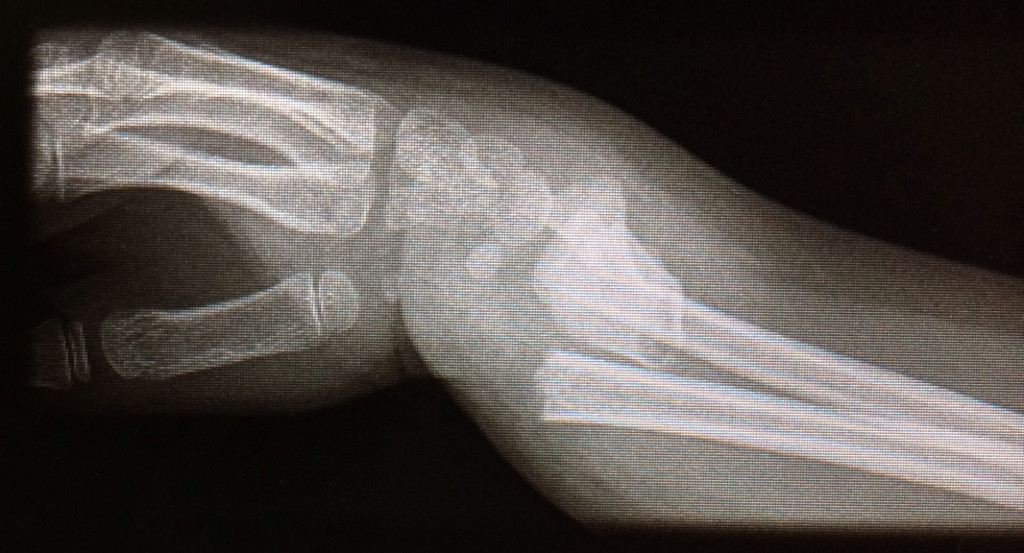

L'examen physique et les radiographies sont essentiels pour le diagnostic précis de ces fractures et pour orienter le traitement. Les radiographies standards peuvent être complétées par un examen scanner si la fracture est intra-articulaire.

Le diagnostic de fracture du scaphoïde se fait à la radiographie standard du poignet. Lors des fractures strictement non déplacée, il est parfois difficile de voir le trait de fracture, et on fait le diagnostic en réalisant un scanner.